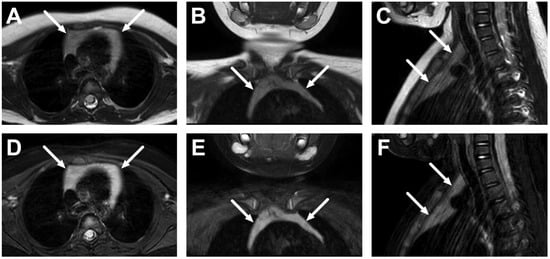

6.1. Mediastinitis